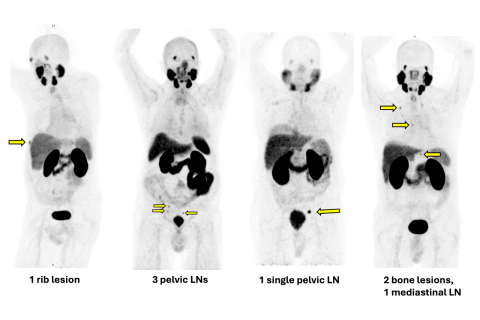

Prostate-specific membrane antigen (PSMA) PET scan: An advanced scanning technology that can locate prostate tumors as well as advanced metastases with unprecedented precision.